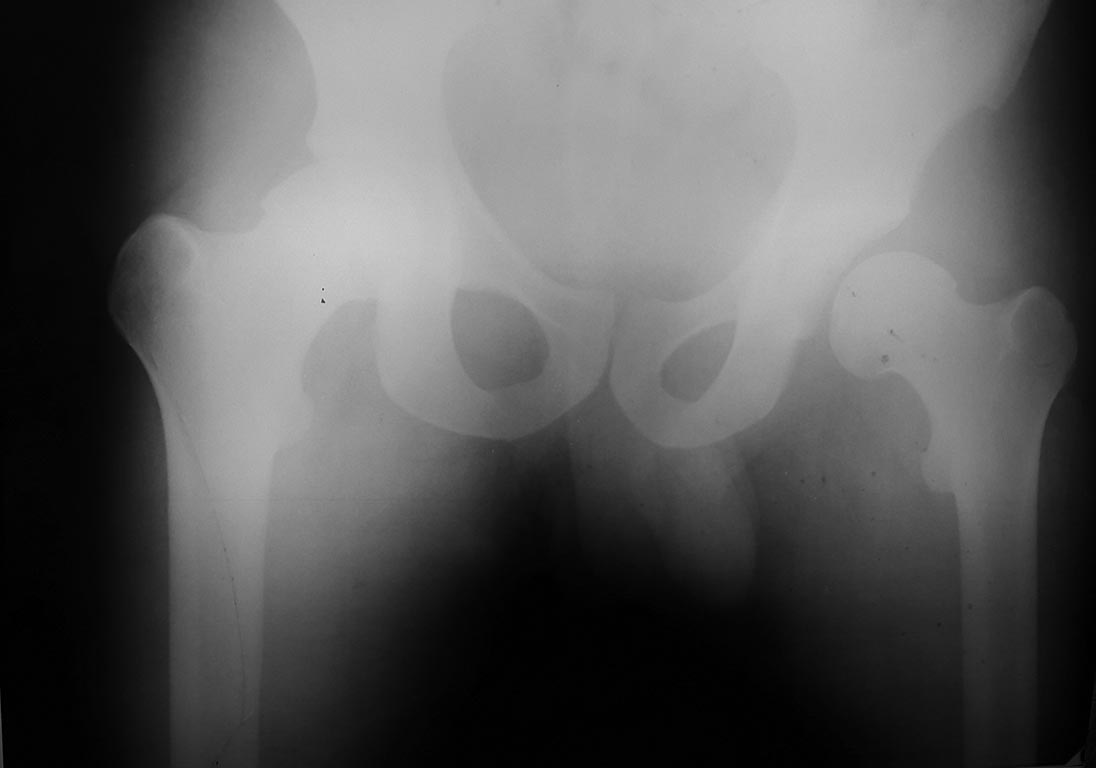

Уважаемые коллеги!Пациент, 24 года, автодорожная травма, неделю назад. Закрытый вывих бедра слева, рваная рана промежности, гематома мошонки. При поступлении вправление вывиха, пхо раны. Деротационная шина.На следующий день-на контроле-повторный вывих повторное вправление, скелетное вытяжение. Rn-граммы и КТ высылаю. Это недовправленный вывих, интерпозиция м/тканей или парез мышц,участвующих в позиционировании головки? Пока на ваытяжении. Что дальше с ним делать? Спасибо.

Случай не самый обычный. Выраженная дисплазия вертлужной впадины. Покрытие головки недостаточное. Того, к чему мы привыкли, когда вправленную головку так просто снова не вывихнешь, здесь не будет. Она и до травмы во многом держалась за счет мягких тканей, которые теперь повреждены. Может и парез каких-то мышц есть, по снимкам не скажешь. Что делать дальше? Наверное снять вытяжение. Какова его цель в данном случае? Если есть ЭОП можно было бы посмотреть, что происходит при вправлении. Действительно ли головка вправляется и в каком положении ноги удерживается в суставе? Если удерживается, попробовать зафиксировать ногу в этом положении (АВФ?). А если не вправляется, думать об открытом вправлении с последующей фиксацией. И что за рана в промежности? Насколько обширная, как заживает, позволяет ли оперировать? И еще, нет ли у пациента разрыва крестцово-подвздошного сочленения?

Простите а где Вы здесь увидели ВЫРАЖЕННУЮ дисплазию. Конечно философски можно любой сустав назвать диспластичным, но ... Ну незначительная может и присутствует не более, я бы назвал это вариантом. Прост за живое задело, раздражает когда слишком часто и необоснованно коллегами выставляется дисплазия тазобедренных суставов. А случай конечно неординарный. Думаю здесь имеет место полный отрыв губы с возможным односторонним разрывом мышц. Прогноз неблагоприятный суставу несомненно не жить. Но в среднесрочной перспективе здесь достаточно простое протезирование, а сейчас конечно открывать и артропластика.

Спасибо за совместное обсуждение. Больному швы сняли? Рана промежности зажила. Планируем в понедельник ревизию и вправление вывиха головки левой бедренной кости.

Спасибо за совместное обсуждение. Больному швы сняли. Рана промежности зажила. Планируем в понедельник ревизию и вправление вывиха головки левой бедренной кости,пластику местными тканями.

Rn-грамма и фото после операции. Со слов коллег( сам не участвовал) была интерпозиция фрагмента мышцы, больше кзади. Еще раз всем спасибо за активное обсуждение.